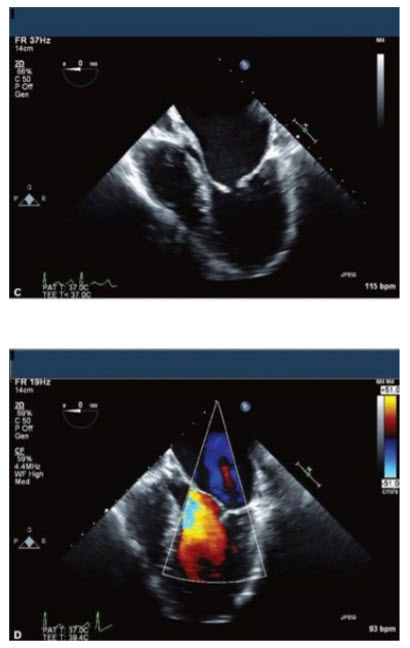

The images in Figure below A–E come from an 18-year-old young man with marked shortness of breath (SOB).

The most appropriate course of action would be

A. Closed mitral commissurotomy because he has a split score of 0 to 4 and minimal mitral regurgitation (MR)

B. Percutaneous mitral valvuloplasty (PMV) because he has a split score of 4 to 8 and minimal MR

C. Surgical MVR because he has a split score of 8 to 12 and minimal MR

D. Surgical MVR because he has a split score of 0 to 4 with significant MR

E. Surgical MVR because he has a split score of 4 to 8 and significant MR